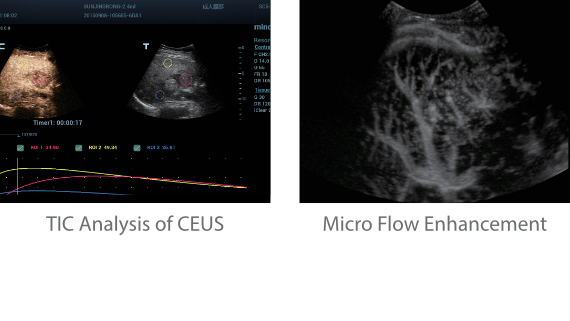

?? Resona 7? ???? ??? ?? ???? ??? ??? ???? ??? ?? ???? V Flow? ?? CNS ??? ?? 3D ??? ???? ?? ???? ?? ??? ?? ?? ?? ??? ??????. ???? ??? ??? ?? ?? ??? ??? ?? ?? ??? ??? Resona 7? ??? ???? ???? ??? ??? ??? ????.